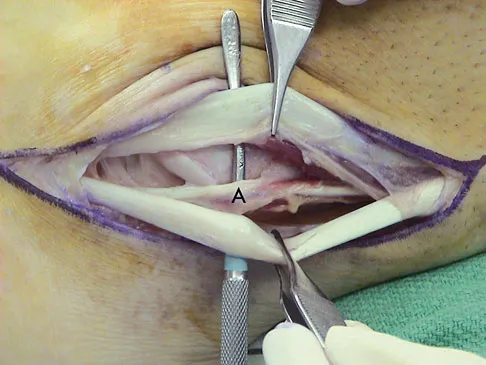

A 35-year-old man is seen for evaluation of his left ankle following multiple previous ankle sprains and frequent episodes of the ankle giving way. Examination reveals marked laxity about the lateral ankle with associated tenderness along the peroneal tendons. Physical therapy, anti-inflammatory drugs, and supportive bracing have failed to provide relief. An MRI scan shows peroneal tenosynovitis and a possible tear. He elects to undergo a peroneal tendon repair and lateral ligament reconstruction. Which of the following best describes the structure labeled "A" in Figure 45?